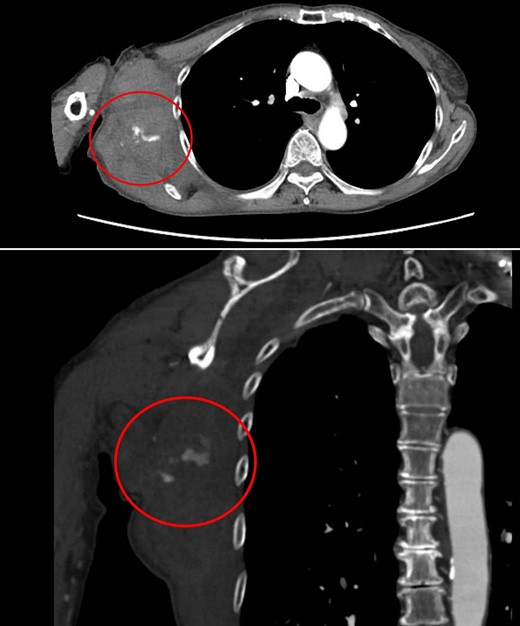

Four days later, the patient was hospitalized for rapidly worsening swelling and pain, and was readmitted with a diagnosis of rebleeding from the chest wall. Physical examination revealed a fist-sized subcutaneous mass on the right side of the chest, with severe pain. Laboratory data indicated anemia (Hb 7.8 g/dl) and no coagulation disorder: % prothrombin time (PT) 115.1%, prothrombin time-international normalized ratio (PT-INR) 0.93, and activated partial thromboplastin time 23.6 s. Computed tomography (CT) at the time of the first hemorrhage showed the hematoma on the right chest and anterior to the scapula (Fig. 2). Contrast-enhanced CT at the time of rebleeding showed an increase in hematoma and extravasation in the peripheral right lateral thoracic artery (Fig. 3). The patient was immediately treated with emergency angiography, which revealed active bleeding from a pseudoaneurysm of the right lateral thoracic artery. Thus, coil embolization was performed (Fig. 4). There were no TAE-related complications and the patient was discharged to home on the fifth hospital day. Oral clopidogrel was resumed and there has been no recurrence of bleeding.

Chest CT at the time of the first bleeding showed formation of a hematoma on the right chest and front of the scapula.